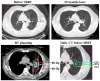

Materials and methods: We delivered SBRT to 27 patients, 13 with Stage I and 14 with isolated recurrent NSCLC. A central/superior location was defined as being within 2 cm of the bronchial tree, major vessels, esophagus, heart, trachea, pericardium, brachial plexus, or vertebral body, but 1 cm away from the spinal canal. All patients underwent four-dimensional computed tomography-based planning, and daily computed tomography-on-rail guided SBRT. The prescribed dose of 40 Gy (n = 7) to the planning target volume was escalated to 50 Gy (n = 20) in 4 consecutive days.